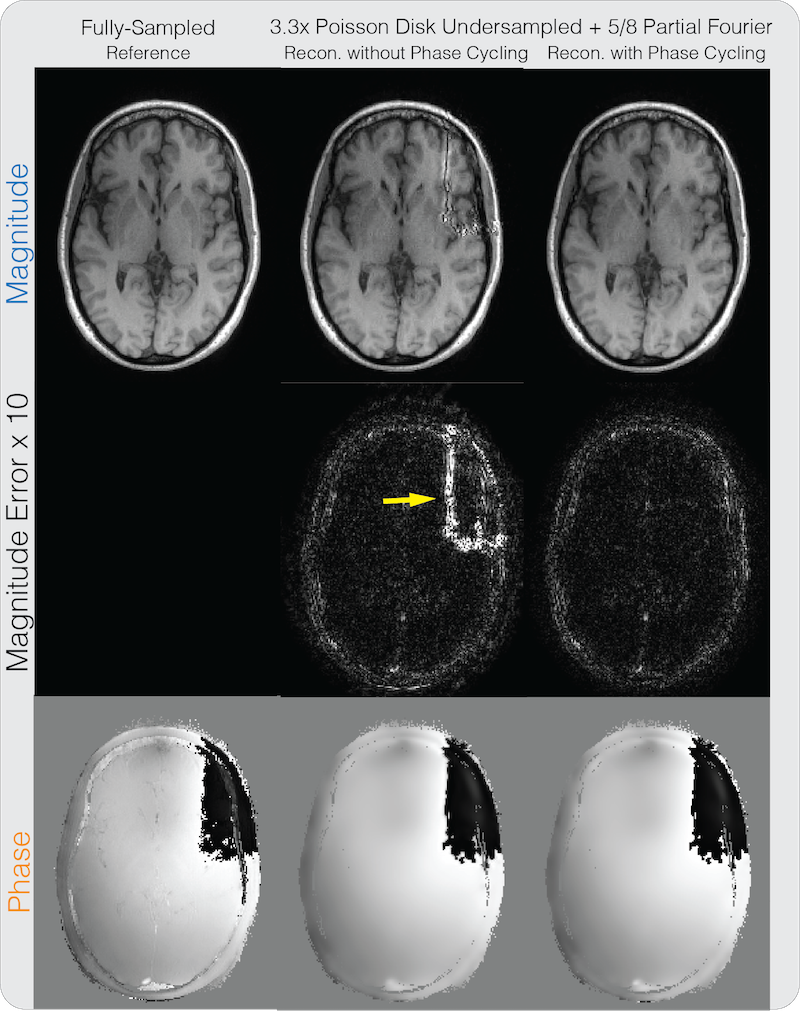

A partial Fourier factor of was retrospectively applied on both datasets. The brain dataset was further retrospectively under-sampled by with variable density Poisson-disk pattern and a calibration region. The proposed method with and without phase cycling were applied on the under-sampled datasets and compared. regularization was imposed on the Daubechies 6 wavelet domain for the phase image. The homodyne method from Bydder et al. [17] with regularization on the wavelet domain was applied and compared. The method was chosen for comparison because it was shown to be robust to errors in the phase estimate as it penalizes the imaginary component instead of enforcing the image to be strictly real. The original formulation included only regularization on the real and imaginary components separately. To enable a fair comparison using similar image sparsity models, we modified the method to impose wavelet regularization on the real and imaginary components separately to exploit wavelet sparsity, which achieved strictly smaller mean squared error than the original method. The number of iterations was set to be 1000. The regularization parameters were set similarly to how the magnitude and phase regularization parameters were selected.

Figure 5 shows the partial Fourier reconstruction results combined with PI and CS on the brain dataset with the proposed method. The figure compares the proposed reconstruction with and without phase cycling. Again, without phase cycling, significant artifacts can be seen in the magnitude image near phase wraps in the initial solution, pointed by the yellow arrow. Reconstruction with phase cycling does not display these artifacts. Figure 6 shows the results for the method of Bydder et al. and Zhao et al. As pointed out by the red arrows, the method of Bydder et al. shows higher error in the magnitude image compared to proposed method with phase cycling in these regions. The method of Zhao et al. shows higher magnitude image error in general, and displays staircase artifacts in the phase image, which are common in total variation regularized images, as pointed by the yellow arrow. In terms of PSNR, the method of Bydder et al. resulted in 33.64 dB, the method of Zhao et al. resulted in 30.62 dB, the proposed method without phase cycling resulted in 30.35 dB, and the proposed method with phase cycling resulted in 34.91 dB. One instance of our Matlab implementation of the proposed method took 1 minute and 53 seconds. We note that the severity of the artifact in the reconstruction without phase cycling for the brain dataset is much stronger than for the knee dataset because a higher regularization was needed to obtain lower reconstruction mean squared error. This is because the brain dataset was further under-sampled for CS. Larger regularization led to larger thresholding errors around the phase wraps and hence more significant artifacts in the resulting reconstructed images.

5.

Partial Fourier + PI + CS reconstruction results on a brain dataset for the proposed method. Similar to Supplementary Figure S1, without phase cycling, significant artifacts can be seen in the magnitude image near phase wraps in the initial solution, as pointed by the yellow arrow.